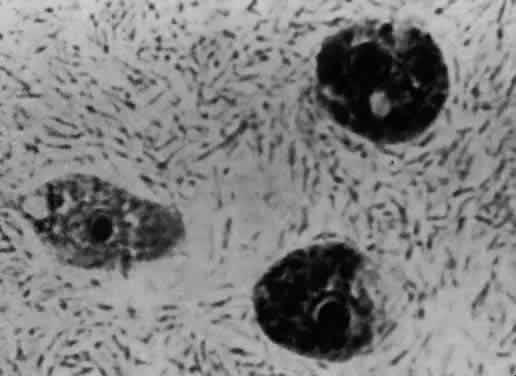

Acanthamoeba organisms are small and resilient, with a wide distribution in the environment.1,2 The protozoan's life cycle is characterized by a transformation from active trophozoite to dormant cyst. The irregularly shaped trophozoite, which is 15 to 45 μm in diameter, is slowly motile (Fig. 1). The cyst is 10 to 25 μm long and has a thick double-walled external structure consisting of an outer wrinkled ectocyst and inner polygonal endocyst (Fig. 2).3,4 Transformation from the trophozoite to the cyst stage enhances survival in unfavorable circumstances, which include wide temperature ranges, desiccation, food depletion, pH changes, low oxygen concentration, and cell crowding.5

Fig. 1. Acanthamoeba trophozoite.

Fig. 2. Characteristic polygonal Acanthamoeba cyst.